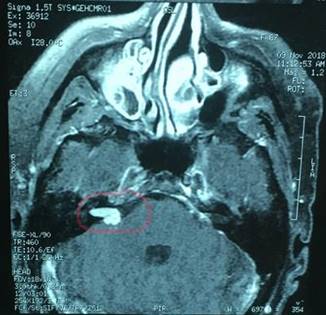

Paciente de sexo femenino, de 67 años de edad, con antecedentes personales de cirugía por tumor del ángulo ponto cerebeloso izquierdo hace 18 años. Se desconoce anatomía patológica. Sordera izquierda secuelar. Presenta hipoacusia en oído derecho y vértigo paroxístico postural. Se solicita resonancia nuclear magnética (RNM) de cráneo que reporta proceso expansivo del ángulo ponto cerebeloso derecho de 15 mm de eje mayor, con una porción cisternal de 8 mm y el resto intracanalicular. No ejerce efecto de masa. Figura 1. Diagnóstico imagenológico de Schwannoma vestibular derecho grado 2 por la clasificación de Koos. Tabla 1.

Figura 1: RNM secuencia T1 con Gadolineo. Se observa Schwannoma Vestibular Derecho con componente intra y extracanalicular (círculo rojo).